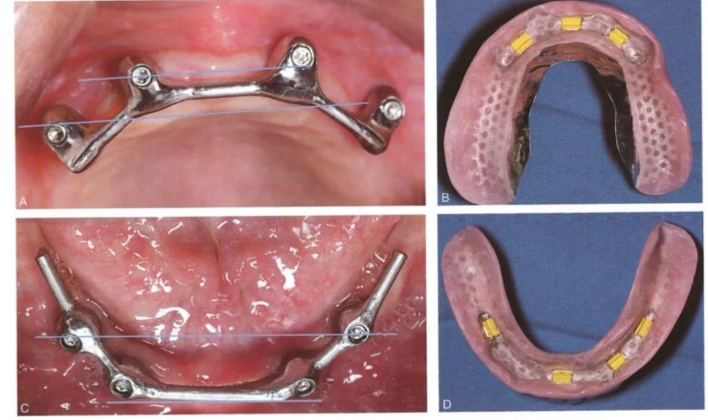

1. 固定原理差异:Locator是在单颗种植体上安装“按扣”装置,患者能像安装手机壳一样自行摘戴;而杆卡需要2颗以上种植体用金属杆连接成轨道,义齿沿轨道滑动,取戴时需要医生协助。

2. 杆卡操作特点:手术时间比Locator多10分钟,因为需要连接金属杆。金属杆需要进行年度检查,这是免费的,而且10年左右可能需要更换金属杆。